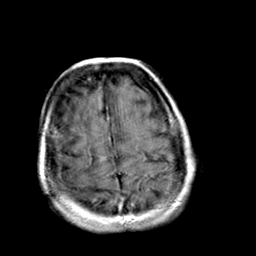

Creutzfeld-Jakob disease: gadolinium enchanced T1-Weighted MR -- Slice #19

[Home][Help][Clinical] Slice 19